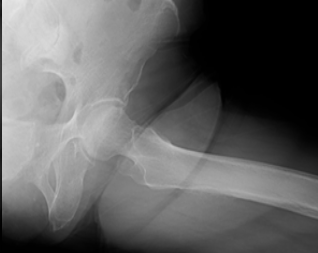

A Rare Case of Left Femoral Neck Fracture in a 6-Year-Old Boy with Osteopetrosis

Sri Harsha Reddy , J K Giriraj Harshavardhan , Sundar Suriyakumar , M Mohammed Tavfiq

………………………………p.216-219